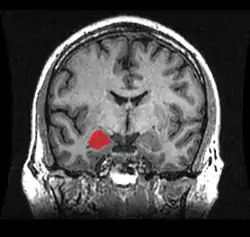

Cuerpo amigdalino

El cuerpo amigdalino, complejo amigdalino o amígdala cerebral es un conjunto de núcleos de neuronas localizadas en la profundidad de los lóbulos temporales de los vertebrados complejos, incluidos los humanos.[1] La amígdala forma parte del sistema límbico, y su papel principal es el procesamiento y almacenamiento de reacciones emocionales.[2][3]